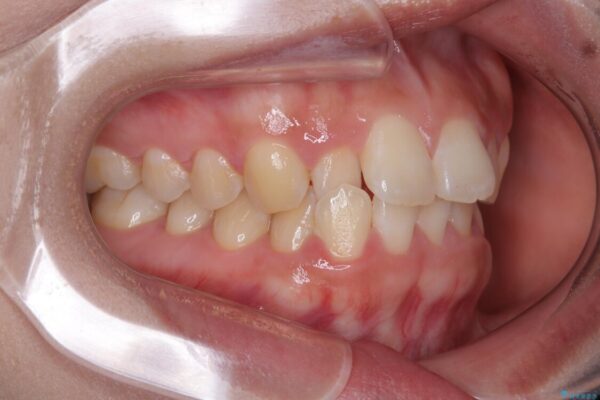

前歯のデコボコが気になるでのことで来院された患者様です。

歯列アーチが狭くスペース不足により前歯がデコボコしている状態でした。見た目を改善しつつ、前歯を前方に突出させず、自然な笑顔を目指したいというご希望でした。

治療前

• 目立ちにくい表側装置で1年完了!狭いアーチを側方拡大し前歯のデコボコを整えた症例 治療前画像